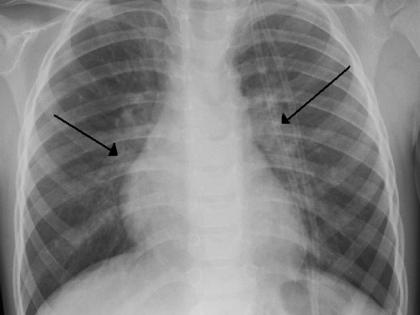

कोरोनाशी लढण्यासाठी फुफ्फुस चांगली असणं आवश्यक; 'या' ५ मिनिटांच्या व्यायामाने राहा निरोगी